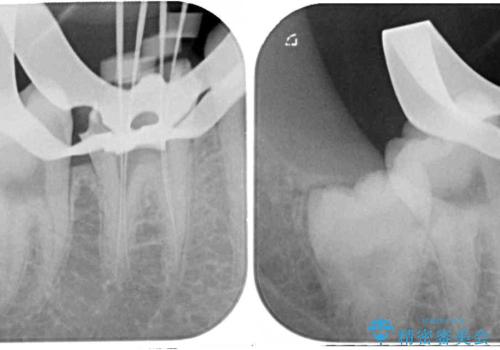

術前の診査では、神経を取り除かなくても済む可能性が示唆されましたが、実際に虫歯除去を進めたところ、レントゲン写真から読み取れる通り、神経組織にまで虫歯が及んでいることが分かりました。

速やかにラバーダム下にて根管治療を行うこととし、その後オールセラミッククラウンにて補綴治療を行うこととしました。

治療期間中、痛みが生じることはなく、処置後3か月経過しましたが良好な状態を保っています。